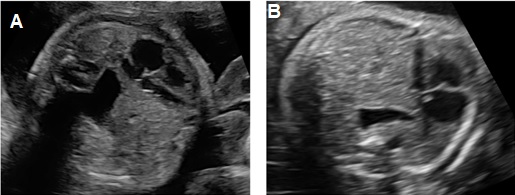

Thoát vị hoành trái: Ở mặt cắt ngang 4 buồng tim có khối phản âm không đồng nhất ở trong lồng ngực trái có thể là dạ dày chứa dịch bên trong (+/-) ruột, gan. Trung thất và tim bị đẩy lệch qua bên phải (Dextroposition). Ở mặt cắt ngang bụng không thấy dạ dày nếu đã bị thoát vị lên lồng ngực.

Thoát vị hoành phải nếu chỉ đơn thuần gan lên có thể khó nhận diện vì phản âm của gan tương tự phổi trên siêu siêu âm thang xám. Hình ảnh đường mật, túi mật là đặc trưng giúp nhận diện gan. Doppler màu có gía trị vì giúp nhận diện các tĩnh mạch gan. Dấu hiệu gián tiếp có thể thấy là hình ảnh trục tim bị lệch.

Hình 2. Thoát vị hoành trái. A: Mặt cắt ngang bụng không thấy dạ dày. B: Mặt cắt ngang 4 buồng tim có hình ảnh dạ dày (DD) và ruột đẩy sát tim qua sát thành ngực phải; phổi phải bị chèn ép.

Hình 3. Thoát vị hoành trái có kèm thiểu sản tâm thất trái